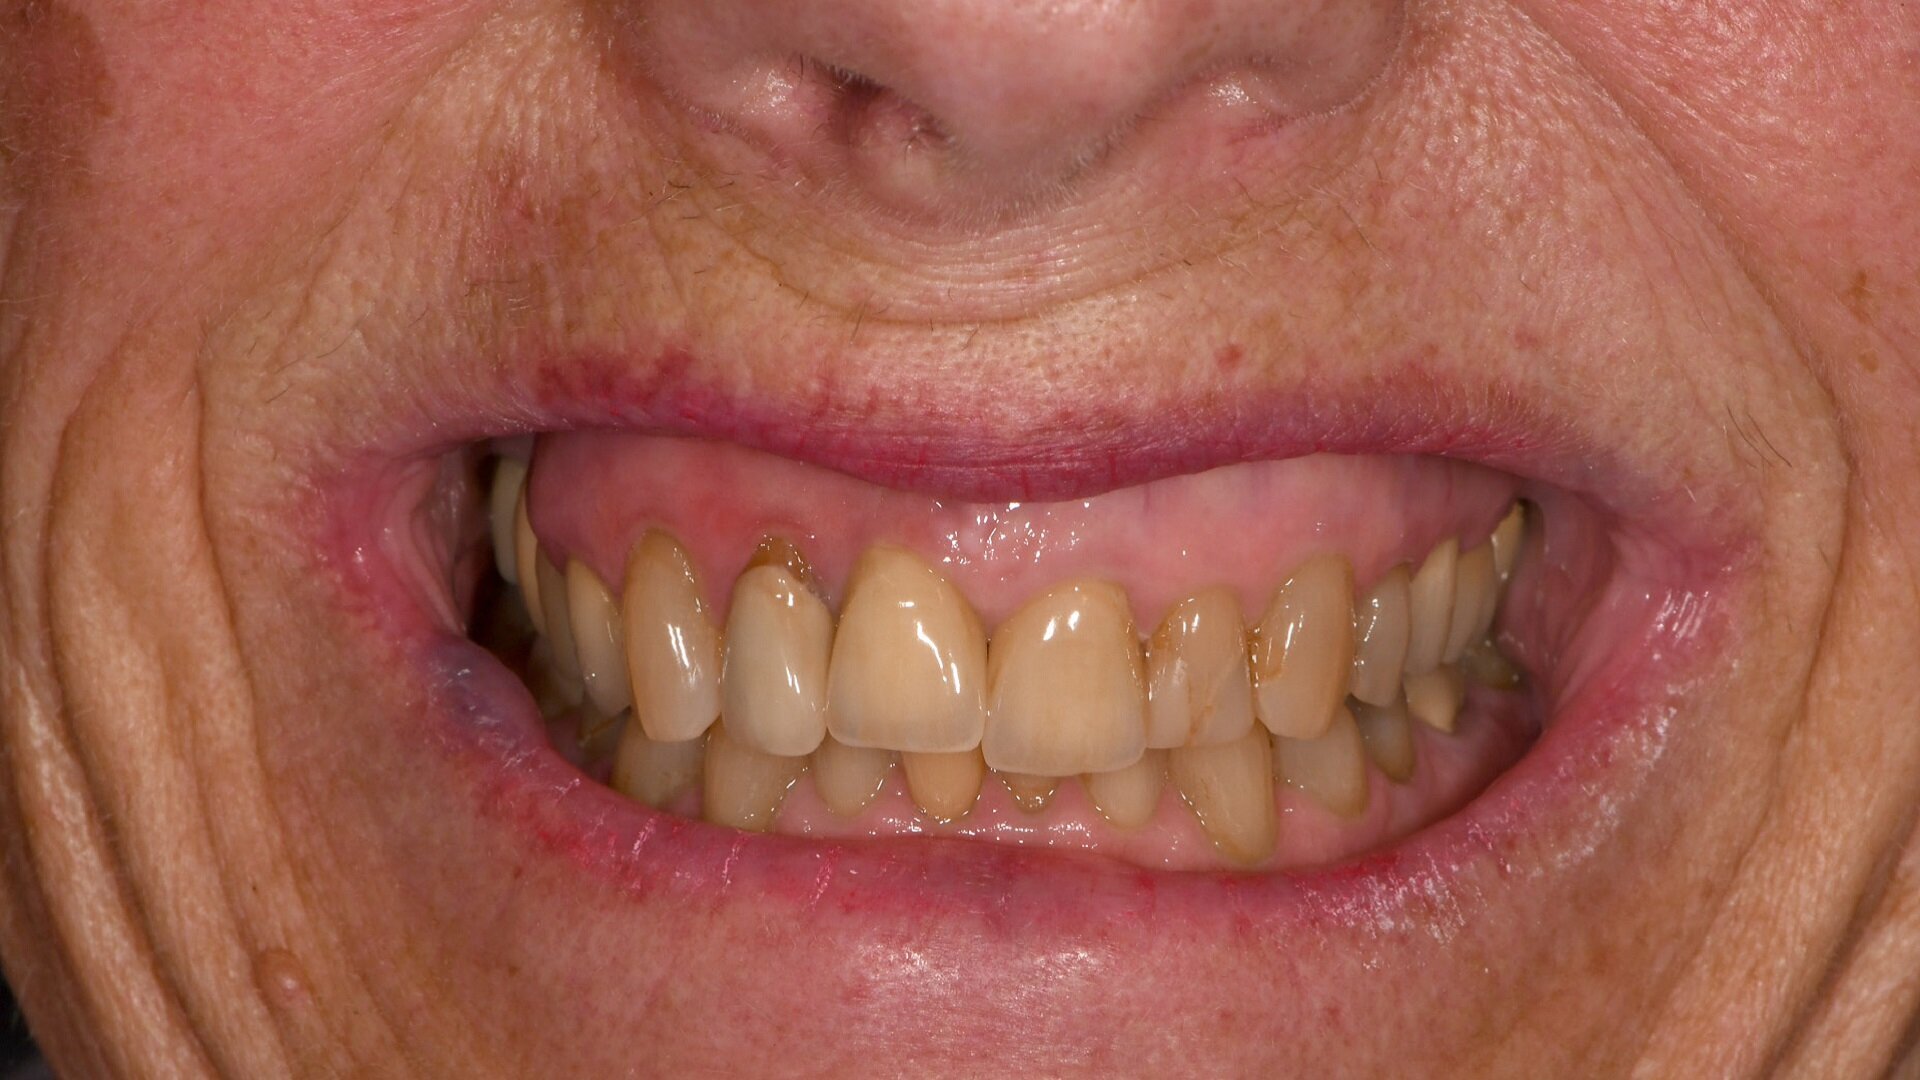

Fig. 9: Long-term temporary restorations in place, frontal view.

After the patient’s approval of the aesthetics, phonetics and function of the temporary restoration, the situation was captured with an intra-oral scanner again. This allowed the team to duplicate the shape of the restoration. Based on the data acquired, two pairs of splinted temporary crowns were milled from PMMA (HUGE Multilayer PMMA, HUGE Dental) in Shade A3 in the laboratory (Figs. 5–7). They were placed to allow the patient to further evaluate the appearance and function for several weeks (Figs. 8–10). The patient was happy with the phonetics, function and appearance of the crowns, noting only that they were slightly too bright in comparison with the adjacent teeth, and she approved the shape for the production of the permanent restorations.